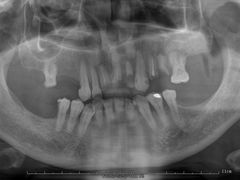

• 牙博士口腔品牌连锁(杨浦店)

• -牙博士口腔品牌连锁(杨浦店)